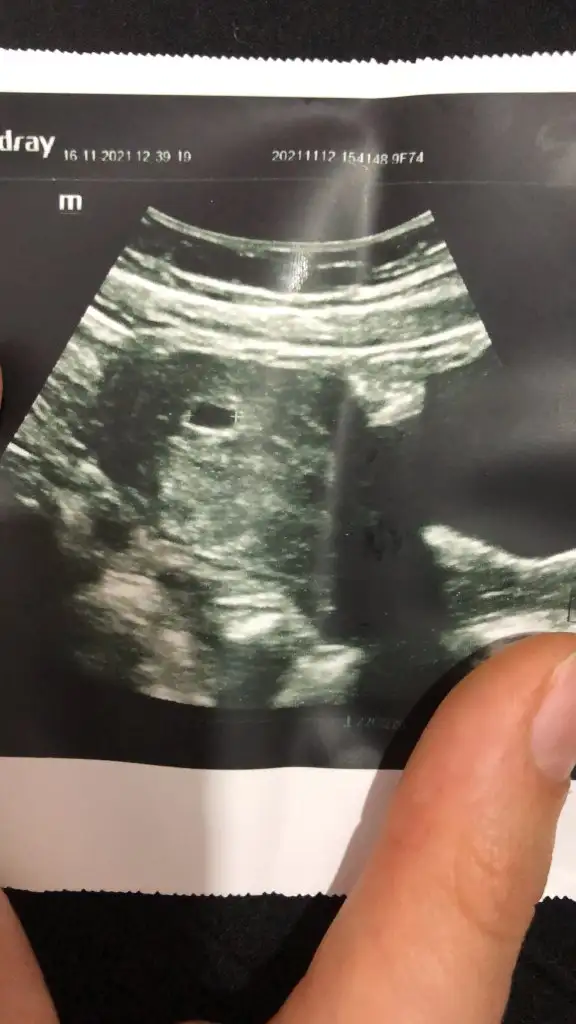

Bebeğin resminide ekledim 😔